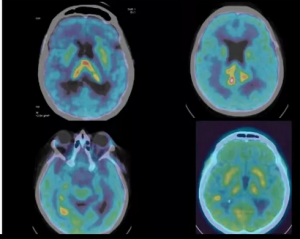

По показаниям могут быть выполнены компьютерная томография (КТ) с контрастным усилением и без него, КТ-ангиография и/или МР-ангиография, МР-трактография, функциональная МРТ (фМРТ) с определением двигательных зон и/или речевых корковых центров, КТ-перфузия и/или МР-перфузия. Также важным дополнительным методом обследования является позитронная эмиссионная томография (ПЭТ), совмещенная с КТ (ПЭТ/КТ), головного мозга с аминокислотами (метионин, тирозин, холин и др.).

• Пациентам с опухолями ЦНС рекомендовано проведение позитронно-эмиссионной томографии, совмещенной с компьютерной томографией головного мозга (ПЭТ головного мозга с аминокислотами (метионином, тирозином) в целях оценки метаболической активности опухоли и повторно в процессе лечения и наблюдения для оценки динамики метаболической активности [5,7].

• При планировании ЛТ для уточнения границ остаточной опухоли пациентам рекомендовано использовать данные МРТ с контрастированием, а также при необходимости ПЭТ/КТ головного мозга с аминокислотами (метионин, тирозин, холин и др.). Объем видимой опухоли (GTV) и клинический объем опухоли (CTV) определяются видом и степенью злокачественности опухоли. Отступ на планируемый объем опухоли (PTV) определяется в соответствии с характеристиками аппарата, системы фиксации и навигации [31].

Комментарии: Для лучшей дифференциации послеоперационных изменений, более точного определения ложа удаленной опухоли в ряде случае при определении мишени целесообразно использовать дооперационные снимки [32]. В зависимости от локализации, объема опухоли, вовлеченности критических структур, предшествующих курсов ЛТ возможно уменьшение отступов и дозы облучения для снижения риска лучевых реакций и развития неврологического дефицита [33]. При рецидивирующем течении, агрессивном поведении опухоли возможна эскалация дозы относительно рекомендованных величин [33]. После проведения ЛТ возможно возникновение отдаленных постлучевых реакций и повреждений головного мозга, в том числе развитие лучевого некроза. Для дифференциации постлучевых осложнений и рецидива опухоли целесообразно использование дополнительного к МРТ с контрастированием ПЭТ/КТ головного мозга с аминокислотами (метионин, тирозин, холин и др.), МР-спектроскопии, КТ-перфузии и др. Для лечения клинически значимых постлучевых осложнений возможно применение стероидной терапии и/или назначение бевацизумаба** [7,26].